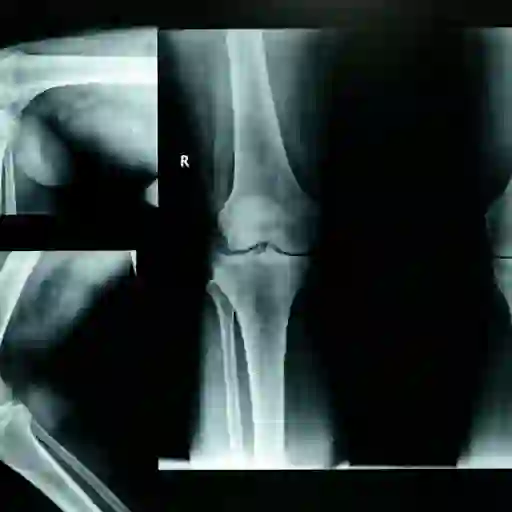

x射线可能没有帮助

如果你报告关节疼痛,x光片通常是医生使用的第一个诊断工具。然而,在疾病初期,x光片可能没有显示出困扰你的关节有任何变化。影响软组织的早期炎症变化很可能无法用普通x光检查出来。只有随着疾病的发展,你才能检测到骨骼结构的变化。